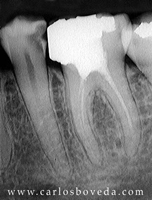

Video de un Retratamiento de Conductos en Una Sesión - (formato Quicktime)